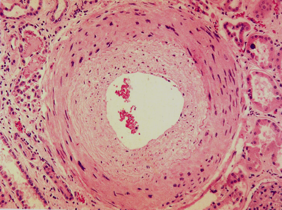

(1)细动脉硬化 细动脉硬化表现为细动脉玻璃样变,是缓进型高血压的基本病变。发生于全身各器官的细动脉(直径<1 mm的、中膜仅有1~2层SMC的最小动脉,如视网膜动脉、脾小体中央动脉、肾小球入球动脉﹚。 由于细动脉反复痉挛,内皮细胞和基底膜受损,内皮细胞间隙扩大,内膜通透性升高,血浆蛋白注入内皮下间隙;同时内皮细胞及中膜SMC分泌ECM增多,继而SMC凋亡,导致管壁发生玻璃样变性。

光镜下,细动脉管壁呈均质红染,管壁增厚,管腔变小。心电图显示左心室轻度肥大。 |

(2)肌型小动脉硬化:主要累及肾弓形动脉、小叶间动脉及脑的小动脉等。由于肌型小动脉长期处于高压状态,其内膜亦有血浆蛋白渗入,内膜胶原纤维及弹力纤维增生,内弹力膜分裂。中膜SMC增生、肥大,胶原纤维和弹性纤维增生。最终导致血管壁增厚,管腔狭窄。